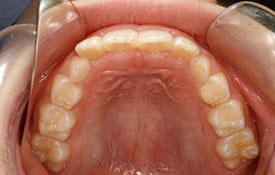

| プロフィール | 15歳 男性 |

| 所見 | アメリカから転院されて来られた方です。 インビザラインで上下顎の矯正治療を開始し下顎はアメリカで終了しており、上顎のみ治療の後期を担当しました。 アイライナーの装着は、1日平均22時間ほどでした。 |